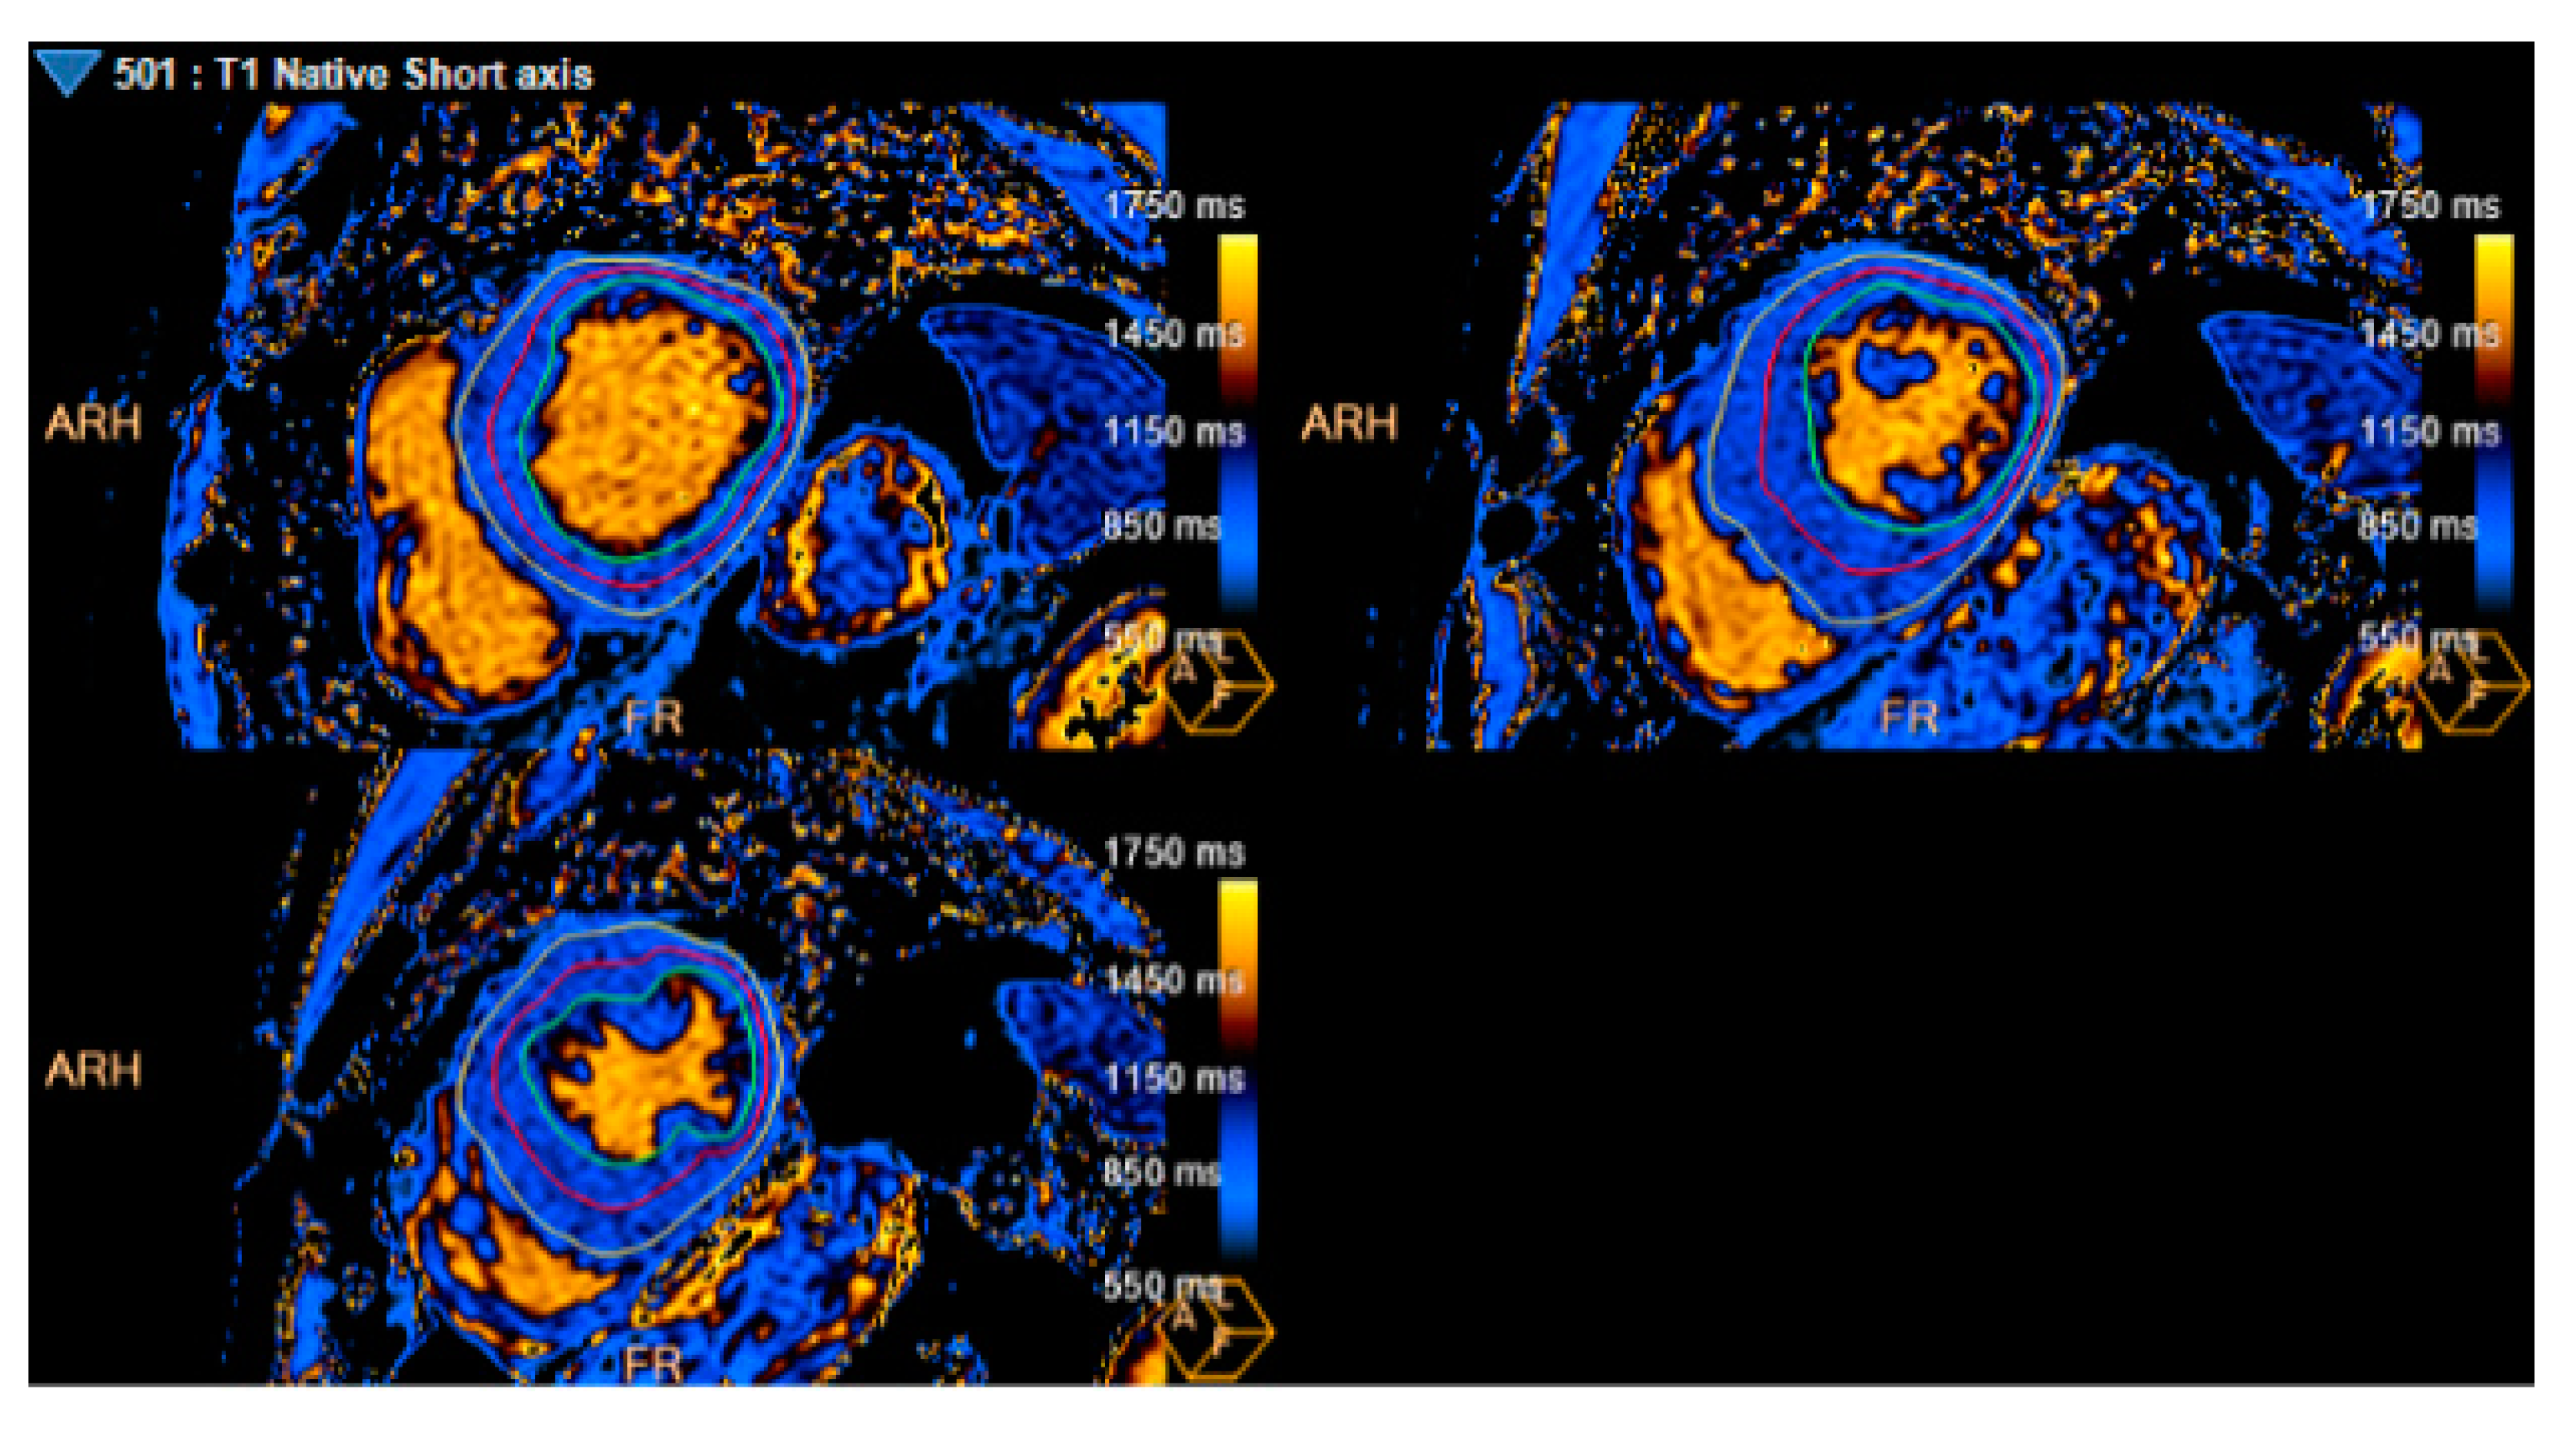

Figure 4. T1 mapping. Average T1 mapping: 929 ms (Measure at basal, mid, and apical LV segments).

Results demonstrated Hemizygosis of the variant NM_000169.3(GLA): c.1066C>T (p. Arg356Trp), described as pathogenic in the galactosidase alpha (GLA) gene, consistent with Fabry Disease (FD). Alpha-Galactosidase A (GAL) levels, in dried blood spots, were 1.09 nmol/mL / h (reference value - RV: 2.0-21.8 nmol/mL/h)), and Lyso Gb3, 5.3 ng/mL (RV: <2.0 ng/mL); also, decreased GLA activity (0.17 mcmol/L/h (RV:1.68-13.63 mcmol/L/h)), and normal activity of Alpha-Glucosidase (2,11 mcmol/L/h (RV:2.10-29.00 mcmol/L/h)). In addition, the case was reviewed by our cardiovascular imaging group and T1 mapping was ultimately performed (Image 4), which reported an average T1 of 929 ms. Extension studies were done, without renal, pulmonary or neurological comprise.

Extra-cardiac involvement includes vessels, kidneys, and peripheral nervous system (6-8). ECG findings other than LVH, such as duration of the P wave < 80 ms and PQ interval < 140ms (as in our patient) have an area under the curve of 0.81-0.92, sensitivity of 80-92% and specificity of 70-80%, respectively. They are useful in early detection, even in the absence of LGE (8). Late onset FD phenotype could present with LVH and papillary muscle hypertrophy mimicking HCM and longitudinal myocardial deformation of the basal segments. The multimodality approach in FD patients is essential, so the use of imaging such as CMR not only provides greater accuracy in the measurement of ventricular wall thickness and can visualize myocardial fibrosis typically distributed in the mid-myocardial layer of the posterolateral wall and extent of fibrosis has been correlated with the degree of response to enzyme replacement therapy (7). The use of tools such as T1 mapping allows the detection of early changes in the cardiac muscle interstitium, and low values, especially at the septal level, have been found in patients with FD, and it is believed that this is directly related to the increase in myocardial lipid tissue (10), thus implying earlier recognition of cardiac involvement by FD. In view of this, the systematic use of CMRI in patients with HP may help to reclassify patients. In this patient and in other with HP phenotype, allowing better risk stratification and therapy targeting. An increased left ventricular end-diastolic thickness with a normal or low T1 mapping such as the one noticed in this patient, should make the clinician suspect and test for FD.

We describe a complex HP case in a patient with an initial diagnosis of HCM due to the severe asymmetric end-diastolic wall thickness by TTE and CMR, which demonstrates the importance of a comprehensive clinical, multimodal imaging approach, and genetic diagnostic tests. All these are necessary to reach a timely and accurate diagnosis. Without forgetting the importance of studying the family group, in a potentially treatable disease. Of note, the T1 mapping (done after the genetic testing) was low (929 ms) for the extent of increased wall thickness, which may have been an initial hint that other conditions such as FD needed to be included in the differential diagnoses. Finally, we suggest some future directions in patients with HP: 1. HP involves a high number of entities with different backgrounds but the same phenotype, so the importance of having some other techniques as multiparametric evaluation can guide us more often to diagnosis. 2. To be alert to the initial red flags in the first steps of the diagnosis of FD for example the use of the ECG. 3. Genetic tests are necessary in the HP to differentiate the phenocopies and to guide the genetic cascade.